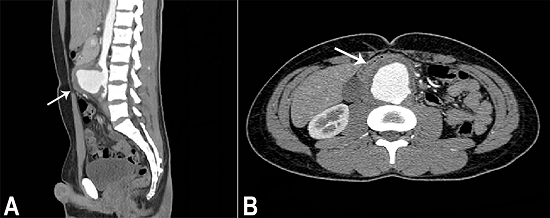

The aortic angiogram computed tomography (CT) revealed an infrarenal aortic saccular aneurysm measuring 6.7 × 5.2 cm (Figure 1).

The aneurysm presented irregular contours and ulcerations, and was surrounded in its entire extension by an irregular dense tissue with fat tissue obliteration (Figure 2A). The aneurysm anteriorly displaced the duodenum and laterally the inferior vena cava and the iliac veins (Figure 2B). The CT findings were consistent with a mycotic aneurysm (MA). The patient was hospitalized and submitted to an endovascular treatment which consisted of the implantation of an aorto-bi-iliac endovascular stent associated with long-lasting empiric antibiotic therapy, which comprised oxacillin and ceftriaxone. A blood culture was sampled before the procedure, but the result was negative. An abdominal CT was undertaken and the patient was discharged clinically well and afebrile, four days after the procedure.